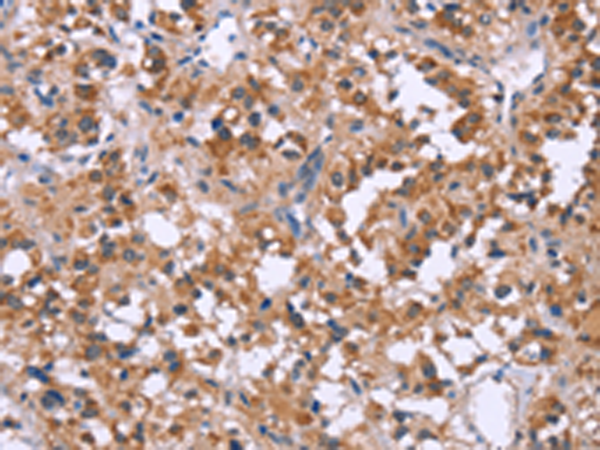

分类: 科研抗体货号: P10660别名: AMPK; AMPKa1应用: IHC反应种属: Human, Mouse, Rat